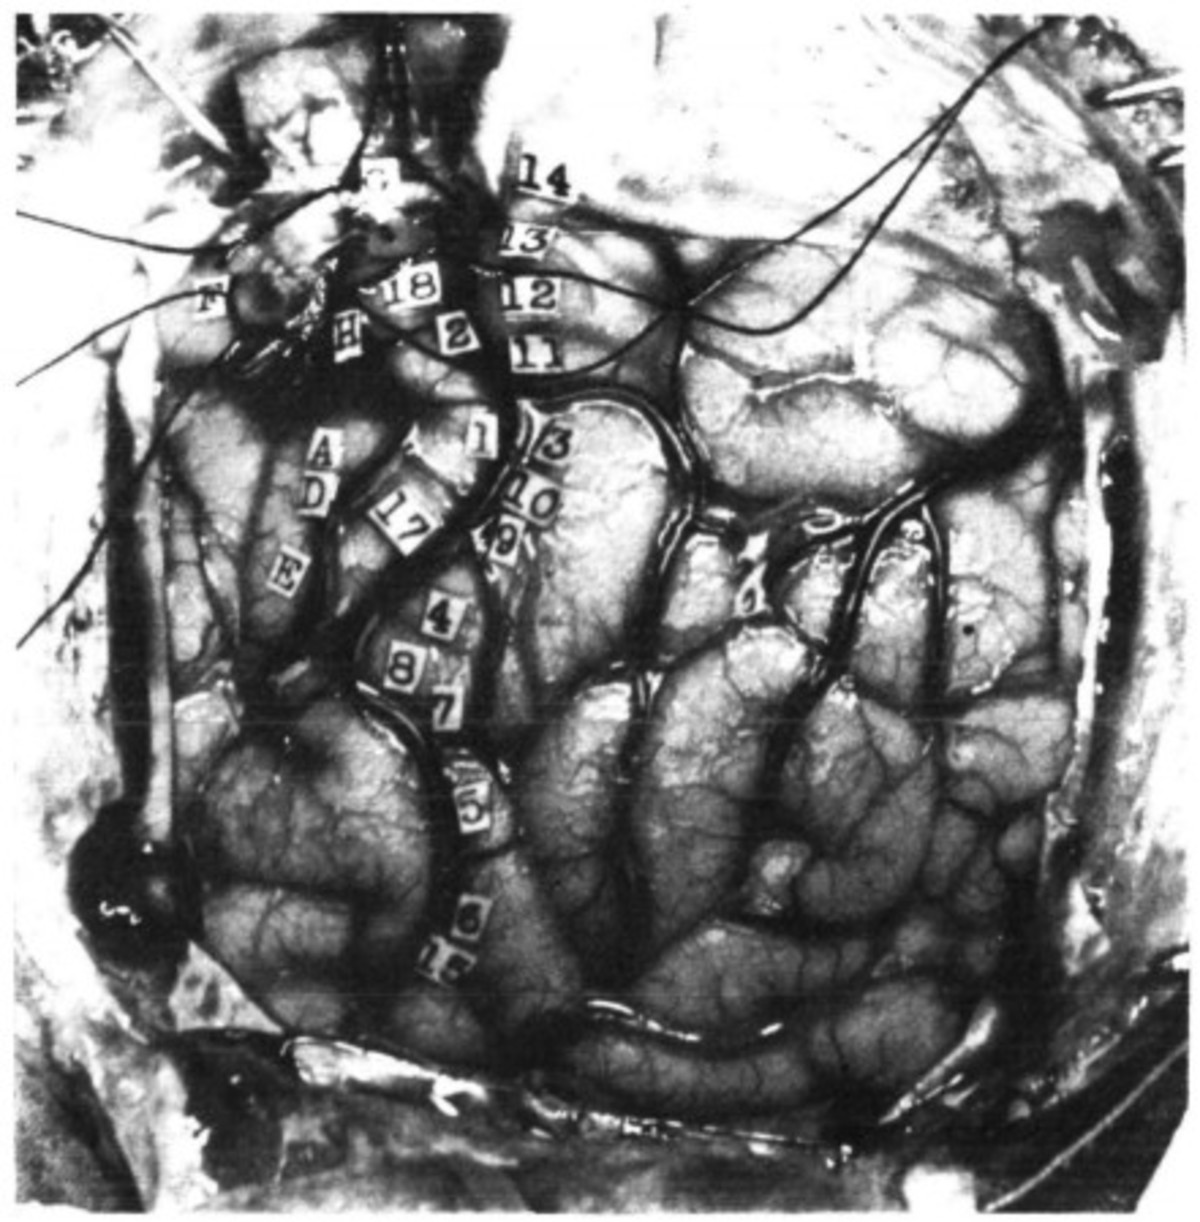

Εδώ βλέπετε μια φωτογραφία πραγματικού εγκεφάλου από μια επιστημονική έκθεση του ίδιου του δρ. Ουάιλντερ Πένφιλντ το 1937 (βλ. τέλος κειμένου για το σχετικό έγγραφο)

Κάθε αριθμός στην εικόνα αντιστοιχεί σε μια συγκεκριμένη λειτουργία του εγκεφάλου και μια αίσθηση που ο δρ. Penfield είχε χαρτογραφήσει. Για παράδειγμα ο αριθμός 18 αντιστοιχεί στην «Ελαφριά συστροφή του χεριού σαν σοκ και (ο ασθενής) αισθάνθηκε σαν να ήθελε να το κινήσει», σύμφωνα με την έκθεση. Στο νούμερο 8, ο ασθενής “αισθάνθηκε αίσθηση κίνησης στον αντίχειρα”, αλλά στην πραγματικότητα δεν κινήθηκε. Στο νούμερο 13, ο ασθενής αισθάνθηκε “μούδιασμα σε όλη την έκταση του δεξιού ποδιού”.